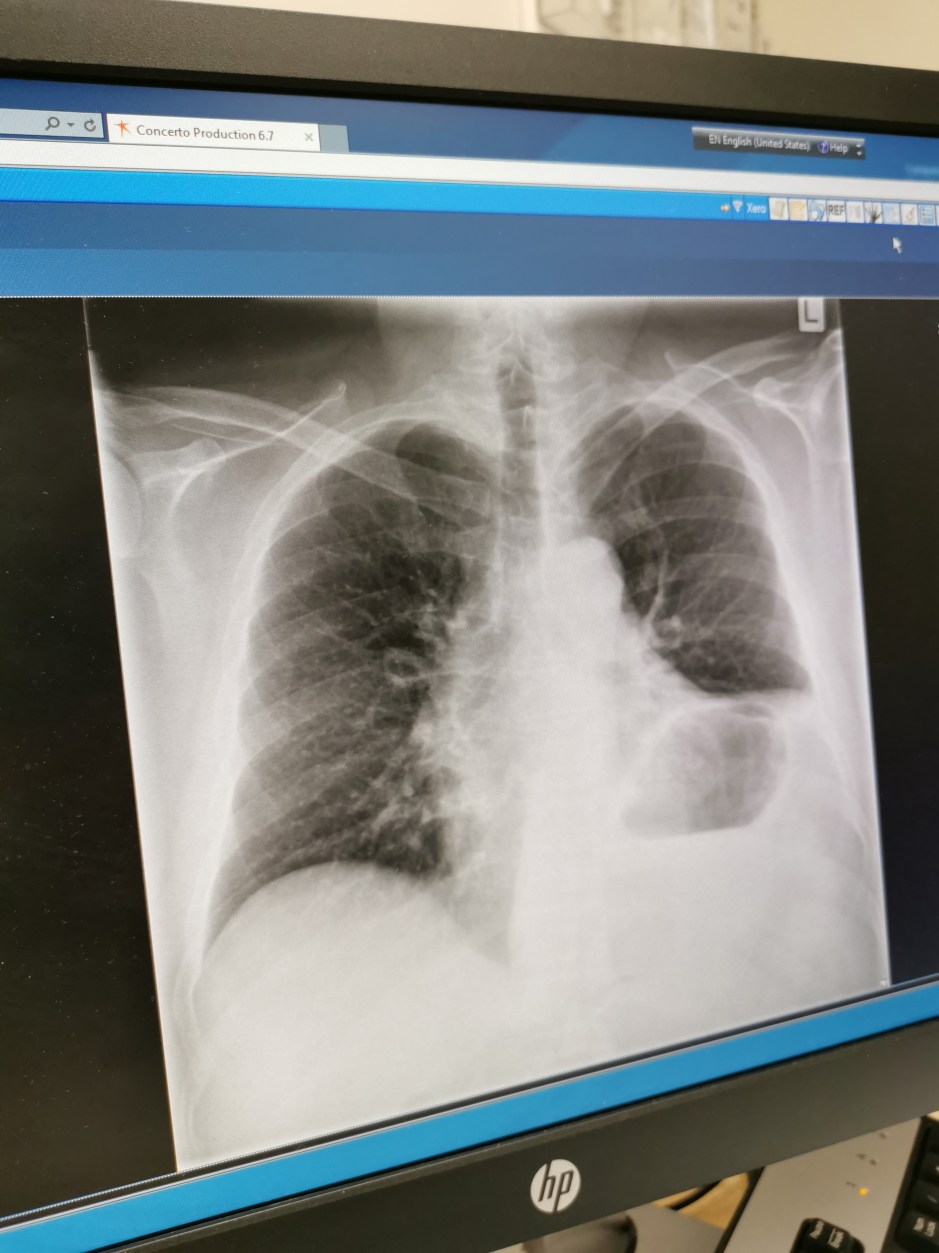

Obviously, I knew that the lymphoma had spread; that’s why it was in my neck. What I didn’t expect was to see a CT report that talked about extensive lymphadenopathy (enlarged nodes) in an area where last year, there was only one enlarged node. It’s also under my arms and inside my left lung. So almost everywhere in my upper chest.

It was also something of a shock to discover that the pressure from these growths is causing even more problems with my phrenic nerve. The phrenic nerve is what drives the diaphragm, and this has contracted due to the pressure. This means that my diaphragm is now so severely elevated on the left side that almost 50% of lung function on that side is lost. At least now, I have a good excuse for being out of breath.